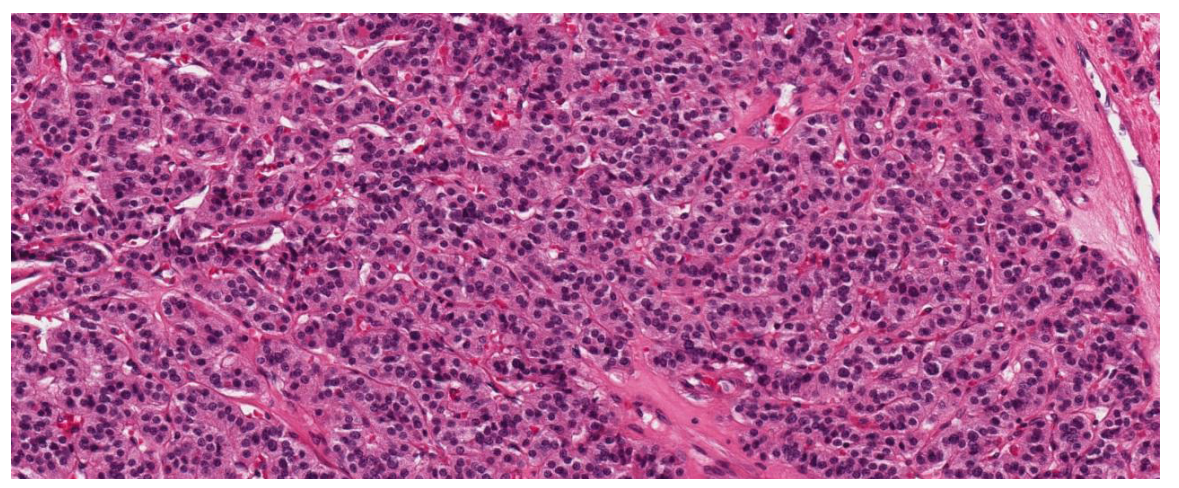

Fig. 1. Poorly differentiated thyroid carcinoma (PDTC) based on the Turin Proposal criteria. Solid/insular growth pattern with thin fibrovascular septa, highly dense small monomorphic cells with high nuclear/cytoplasmic ratio; no nuclear features typical for papillary thyroid carcinoma (H&E, ×200 magnification)